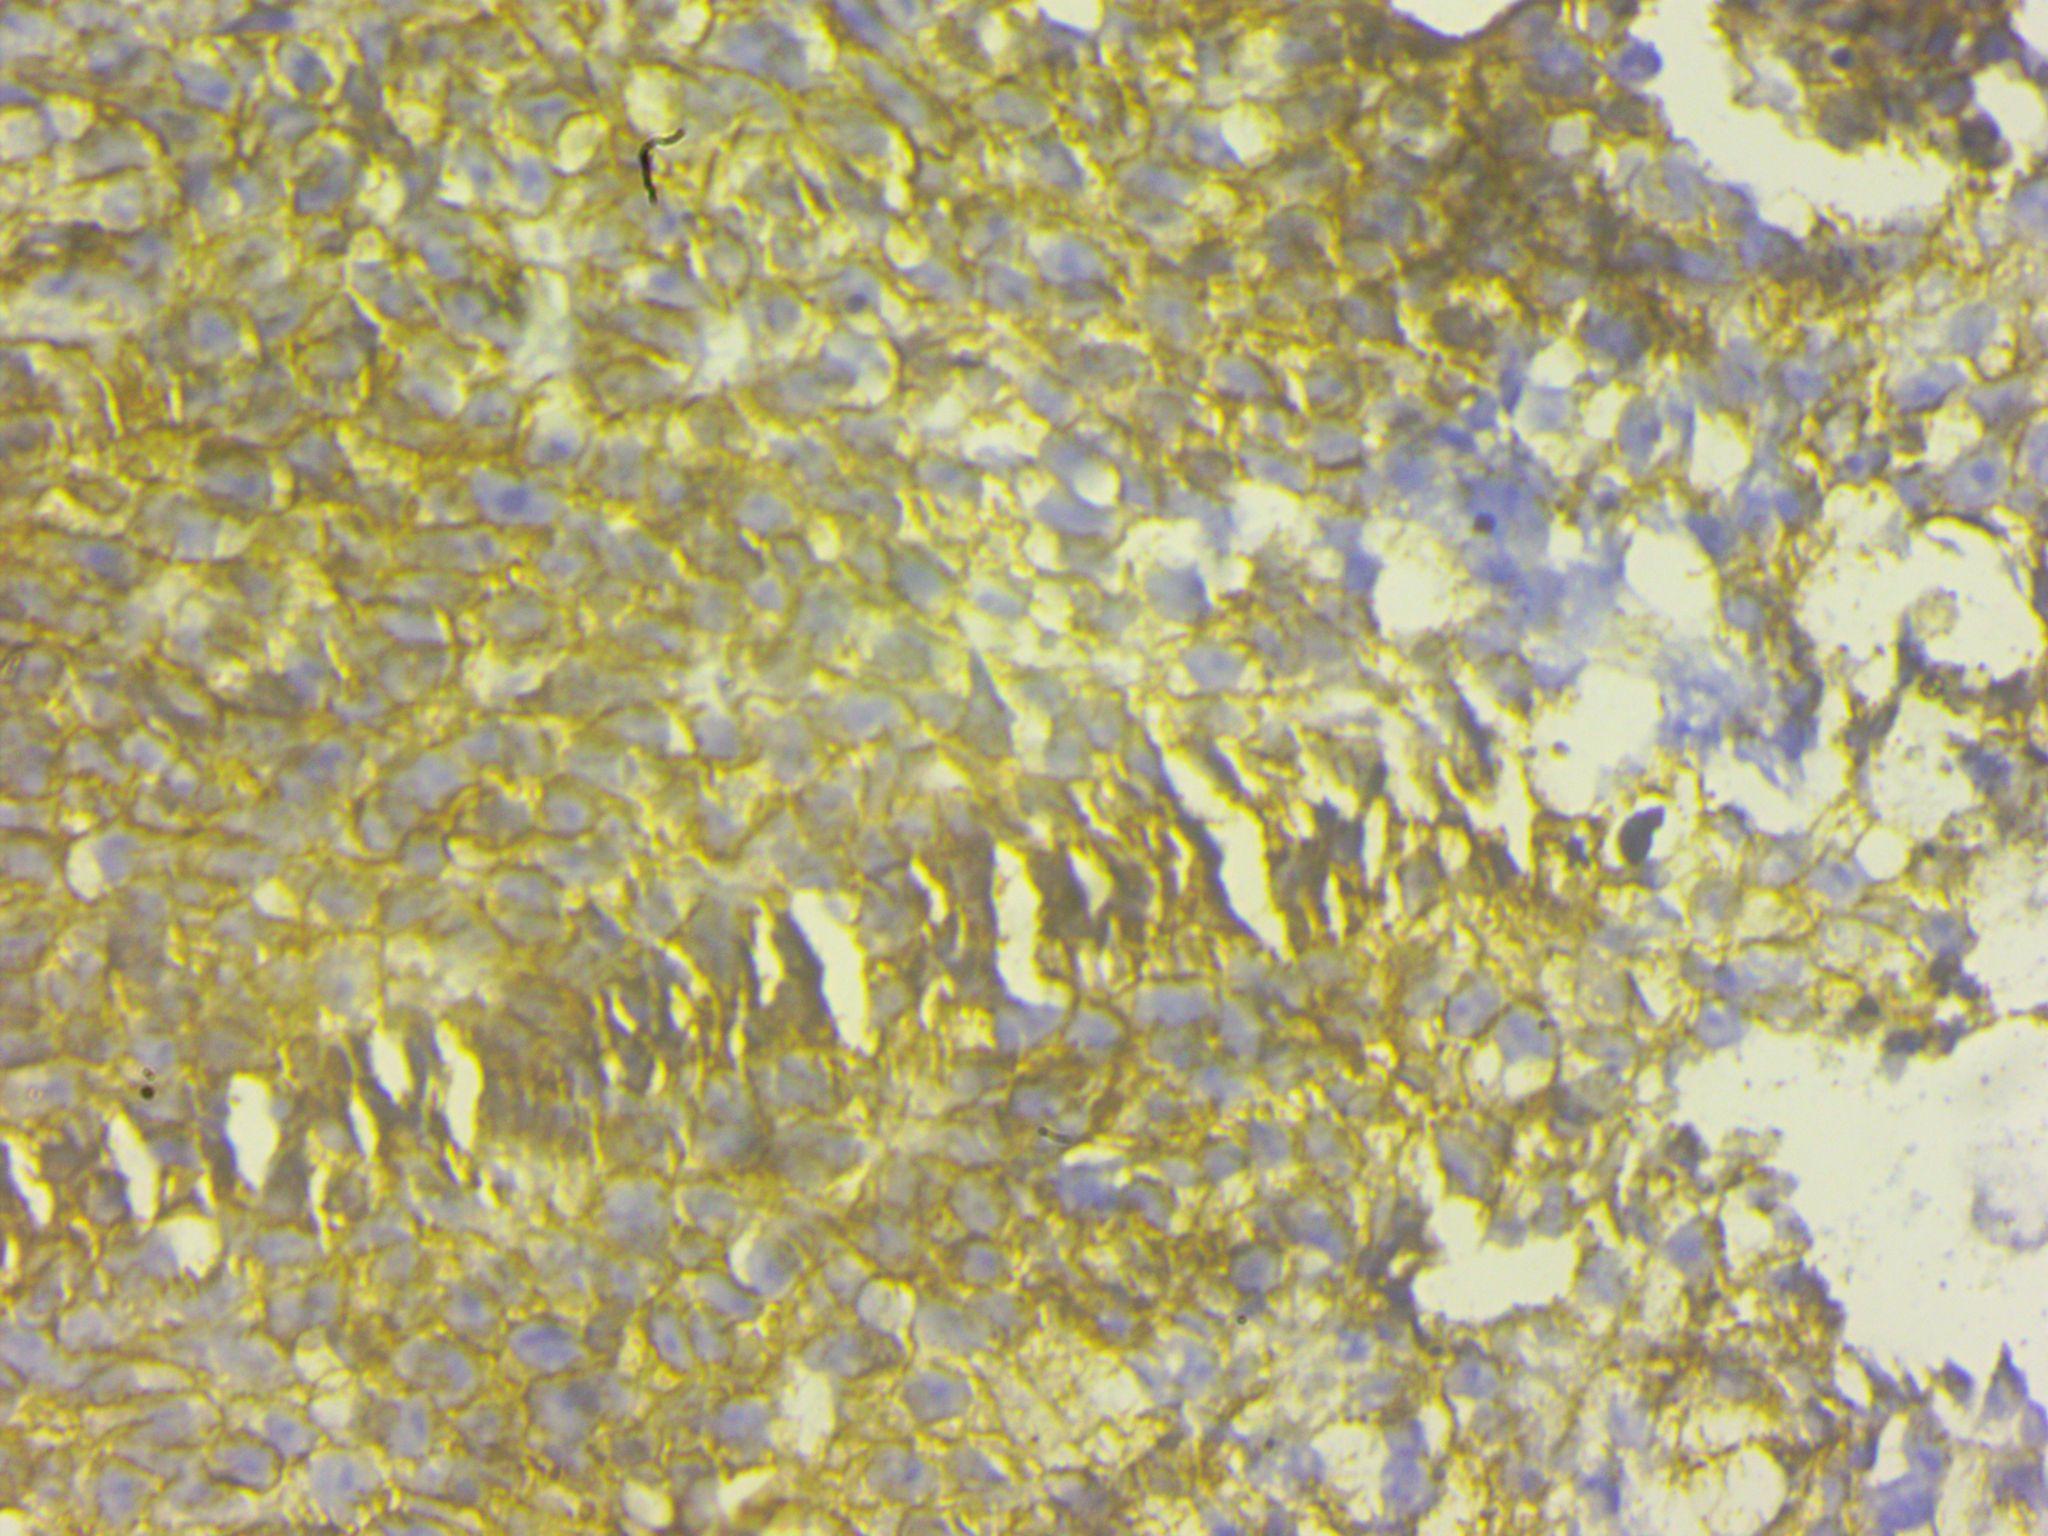

A transurethral biopsy of the mass was performed. Histopathological analysis revealed clusters of small round blue cells infiltrating the prostatic tissue. Immunohistochemistry study revealed a high degree of CD99 positivity and diagnosis of prostatic PNET was made.

Histopathological characteristics are crucial in making the diagnosis of a prostatic PNET. PNET appears as a mass of small, round undifferentiated cells cluster densely packed in a lobulated, nest-like, or flaky pattern under a light microscope. Over 90% of PNETs have the EWS-FLI1 fusion gene positive and exhibit a translocation between chromosomes 11 and 22's long arms. PNET's characteristic round cells react to antiCD99 antibodies (Mic-2).[8] A large number of cases follow the diagnosis scheme developed by Schmidt et al, It involves the existence of Homer-Wright rosettes and/or the expression of two or more neural markers.[9] In our case CD99 IHC marker was positive in tumor cells. Radiotherapy, chemotherapy, and surgery combined can be a successful treatment plan for PNET of the prostate. It is common practice to recommend the chemotherapeutic drugs vincristine, doxorubicin, cyclophosphamide, etoposide, and ifosfamide.[8] In 177 patients with localized Ewing's sarcoma, Dunst found that radiotherapy was equally effective in terms of overall survival as surgery or a combination of surgery and radiotherapy. For localized PNET of the prostate, chemotherapy is a potentially useful treatment option, albeit a standard protocol has not yet been established.[10]